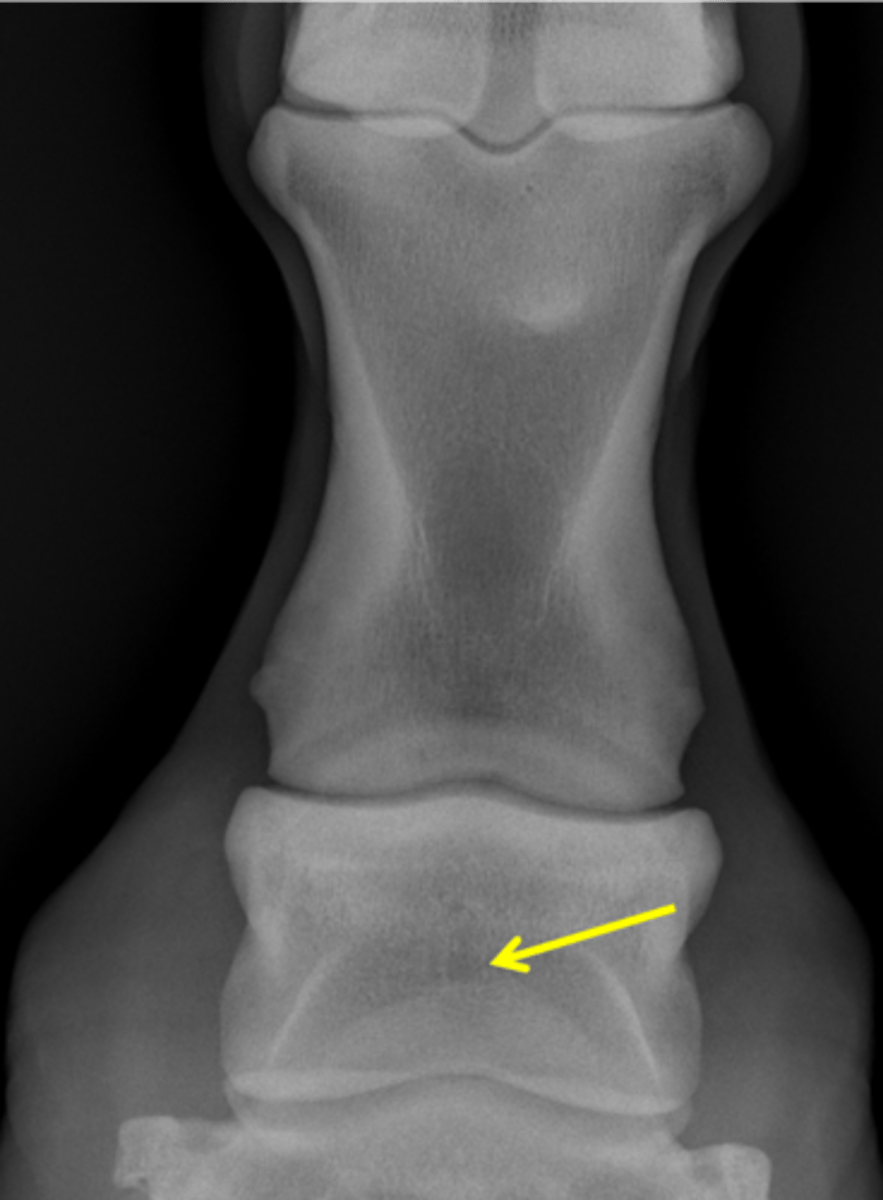

Fetlock joint, DP

ID joint and view

Palmar process of P2

Proximal sesamoid bones

Sagittal ridge

Attachment of collateral ligaments

Proximal sesamoid bones

Palmar process of P1

Condyles of the third metacarpal bone